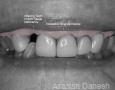

Pictures

Baseline